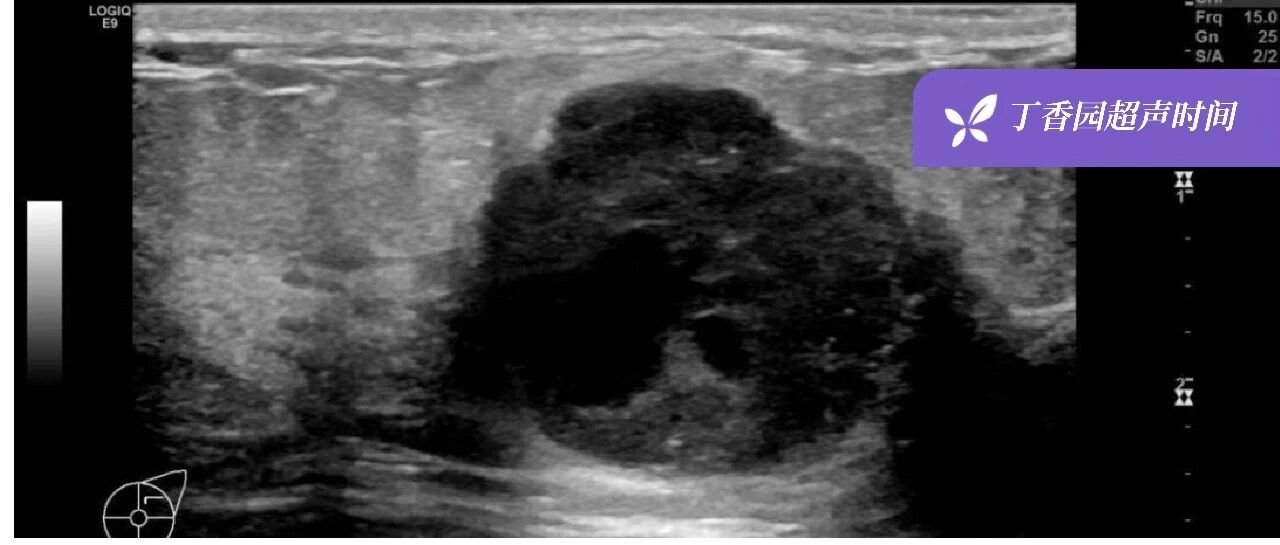

超声诊断「乳腺化生性癌」1 例